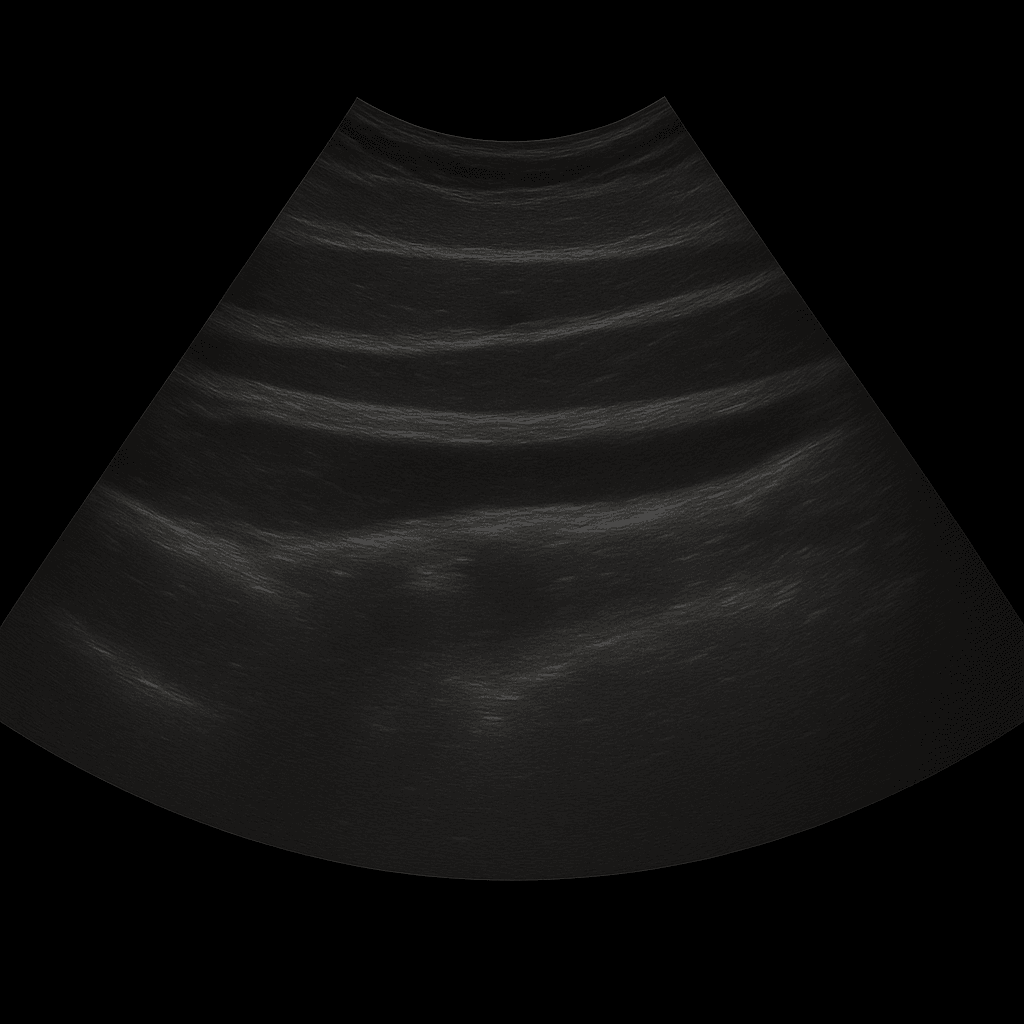

Ett ultraljud av bukväggen används för att undersöka hud, underhud och muskulatur i bukväggen. Undersökningen utförs av specialistläkare inom radiologi och ger detaljerade bilder i realtid som kan visa förändringar som orsakar smärta, svullnad eller synliga utbuktningar i buken. Ultraljud bukvägg används ofta vid misstanke om bråck, vätskeansamlingar, hematom eller andra förändringar i mjukdelarna.

Till skillnad från MR och DT, som används för att kartlägga djupare organ och strukturer i bukhålan, är ultraljud förstahandsvalet för att undersöka ytliga förändringar i bukväggen. Ultraljud visar muskulatur, vävnadslager och eventuella defekter i realtid – utan strålning eller kontrastmedel.

Undersökningen utförs medan du ligger på rygg. En gel appliceras på huden och läkaren för ultraljudsproben över det område där du har besvär. Bukväggen undersöks i olika plan, både vid vila och under lätt anspänning, vilket gör det möjligt att se eventuella bråck eller defekter som framträder när buken belastas.